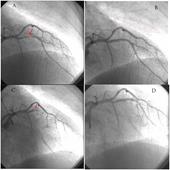

Khi chụp mạch vành, bác sĩ của bạn sẽ chỉ cho bạn thấy động mạch vành bị hẹp/tắc, vị trí tắc nghẽn và mức độ tổn thương, có cần phải can thiệp nong và đặt stent hay không. Tên và nhánh của các động mạch vành được chỉ ở hình 1.

Khi ở trong phòng can thiệp, bạn sẽ được chuyển lên bàn can thiệp. Chụp và can thiệp động mạch vành có thể được tiến hành qua động mạch vùng bẹn, khuỷu hay cổ tay. Vùng làm thủ thuật sẽ được làm sạch và cạo lông, sát khuẩn sạch và phủ vải vô khuẩn xung quanh. Bác sĩ làm thủ thuật sẽ gây tê vùng đó bằng thuốc tê trước khi mở một lỗ nhỏ vào lòng động mạch tại vùng đó. Tiếp theo, một ống nhỏ (được gọi là sheath) sẽ được đưa vào động mạch. Qua ống này, một catheter dẫn đường đặc biệt sẽ được đưa vào để lái theo động mạch đến động mạch vành. Sau đó, một dây dẫn rất nhỏ và mỏng được luồn qua ống thông trên để đưa đến vị trí tổn thương rồi xuyên qua chỗ tắc trong lòng động mạch vành. Tuỳ thuộc vào tổn thương của động mạch vành, bác sỹ có thể dùng một bóng nhỏ đặc biệt đưa vào nong chỗ hẹp tắc trong động mạch vành hay không. Quả bóng này giúp mở chỗ tắc bằng cách ép mạnh mảng xơ vữa vào thành mạch làm mở thông động mạch. Có thể cần nong một vài lần tiếp theo với những cỡ bóng to hơn hay với áp lực cao hơn để giảm mức độ tắc nghẽn. Thông thường, nong động mạch vành bằng bóng có thể làm mức độ hẹp giảm đi từ 20 - 30%. Cuối cùng, một hoặc một vài stent sẽ được đặt vào vị trí tổn thương để giảm tỷ lệ tái hẹp sau can thiệp.